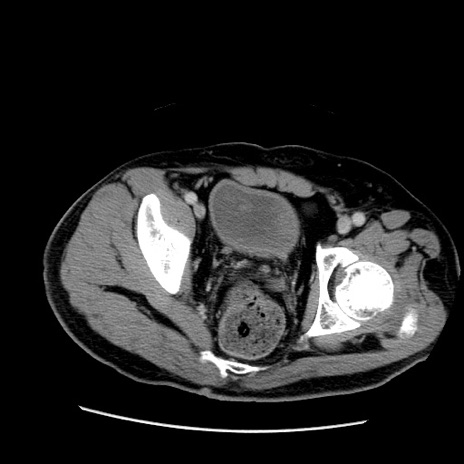

症例

冠状断像